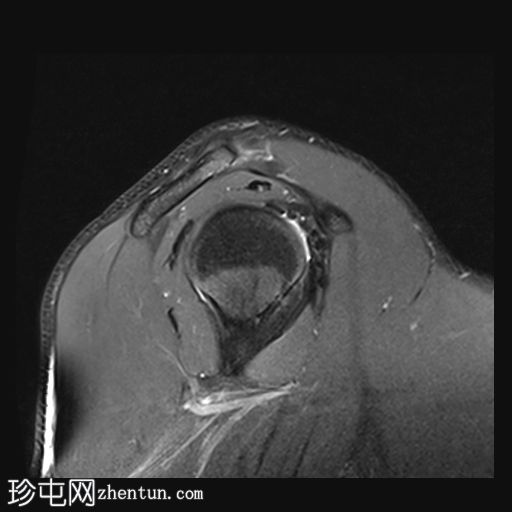

冠状位PD序列

脂肪抑制序列

肱骨头后外侧骨缺损,伴有骨髓挫伤,符合近期肩关节前脱位引起的急性Hill-Sachs损伤。

前下盂唇撕脱,骨膜附着完整,提示软性Bankart损伤。

肩胛盂下韧带前束在盂肱关节附着处断裂,符合GAGL(肩胛盂下韧带)的特征,盂肱关节下方可见关节囊外积液,并伴有盂唇旁囊肿。